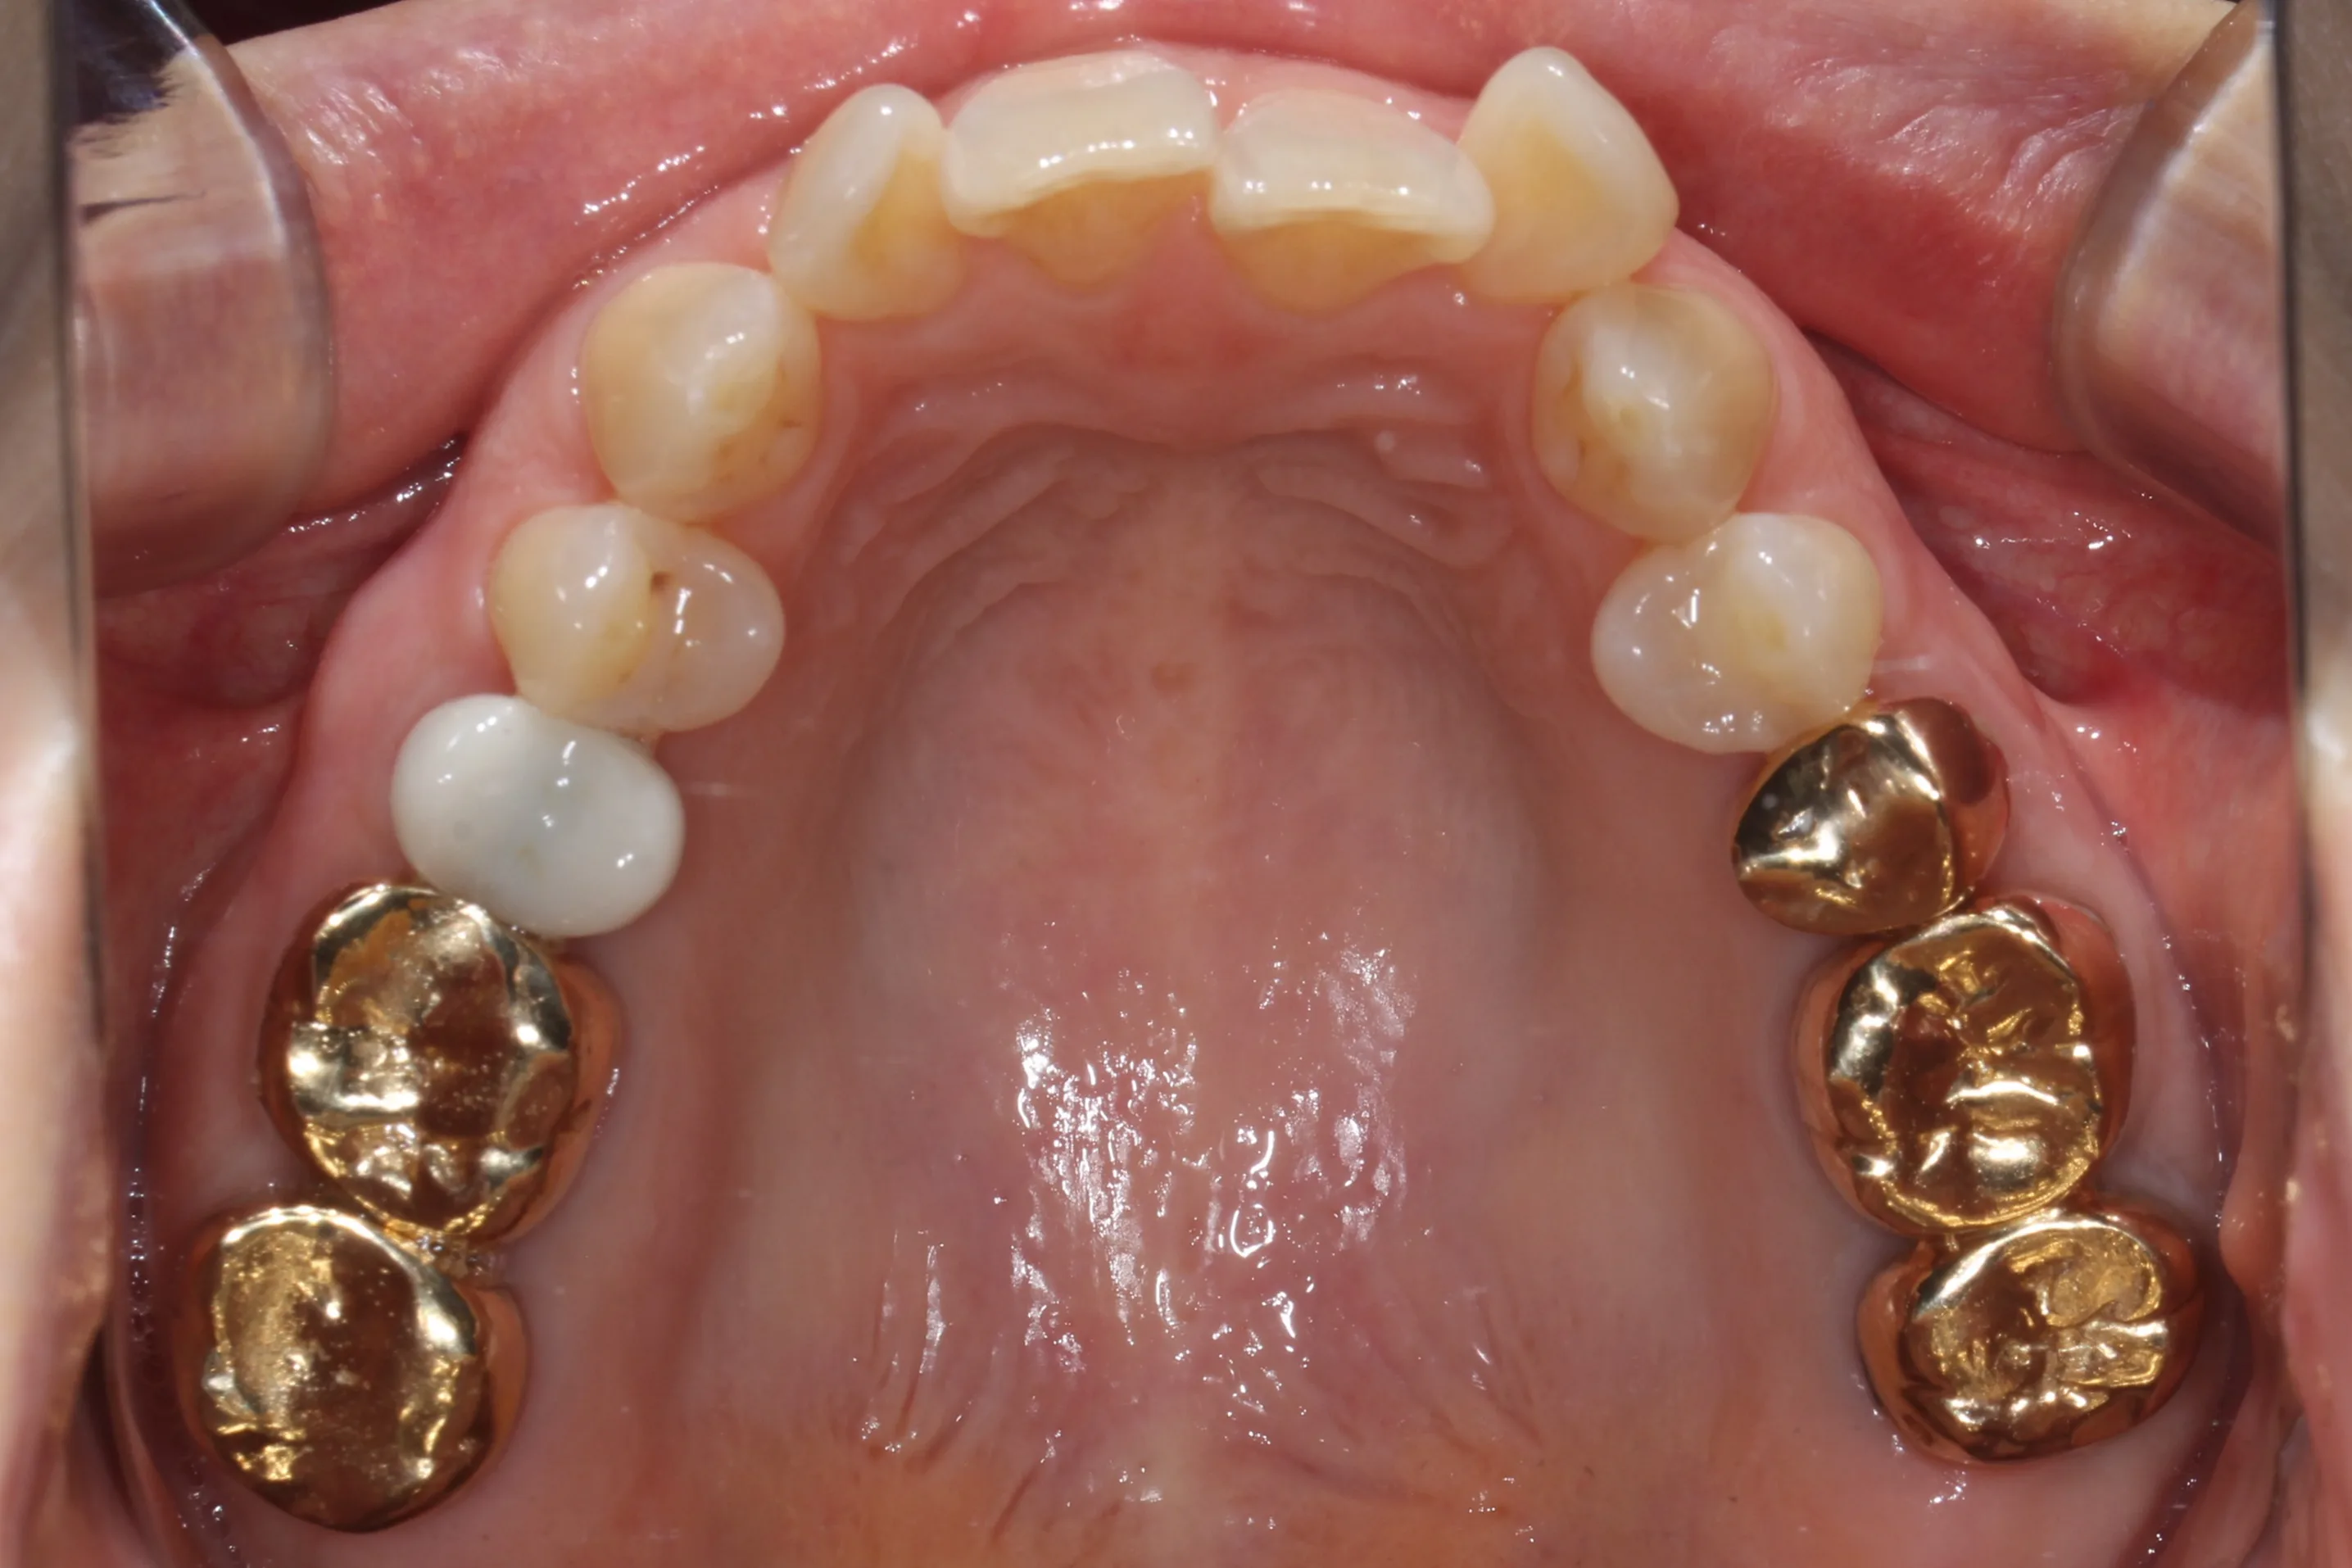

이 환자분은 이미 구강 안에 여러 개의 임플란트와 브릿지 보철물이 있는 상태였습니다. 앞니는 가지런하지 않고, 윗니가 아랫니를 깊게 덮는 과개교합(deepbite)도 있었습니다. 이런 경우 가장 중요한 것은 기존 임플란트와 보철물의 교합을 그대로 유지하면서, 나머지 치아만 가지런하게 배열하는 것입니다.

인비절라인의 디지털 치료 계획을 활용해서, 임플란트와 보철물이 있는 어금니는 움직이지 않도록 고정하고 앞니 위주로만 이동시켰습니다. 덕분에 발치 없이, 고무줄이나 미니스크류 같은 추가 장치 없이도 15개월 만에 치료를 마무리할 수 있었습니다.